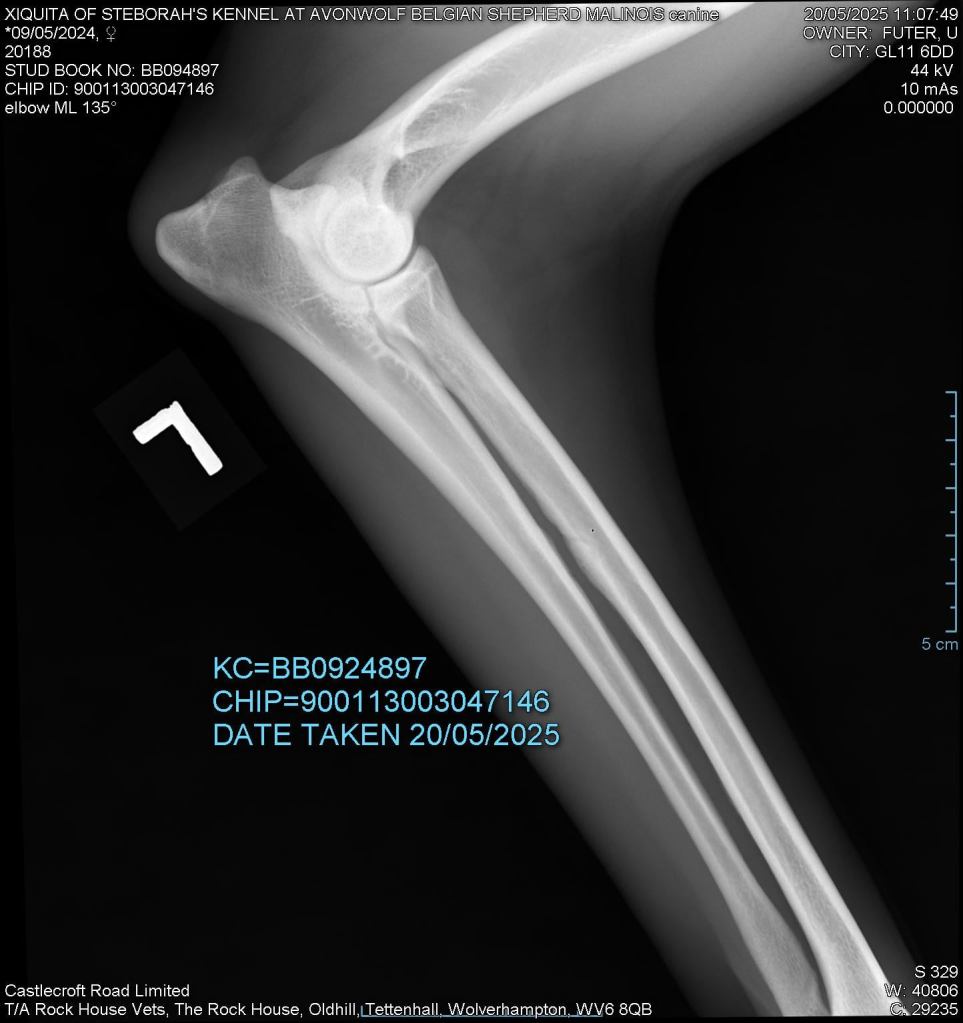

Elbows 0/0